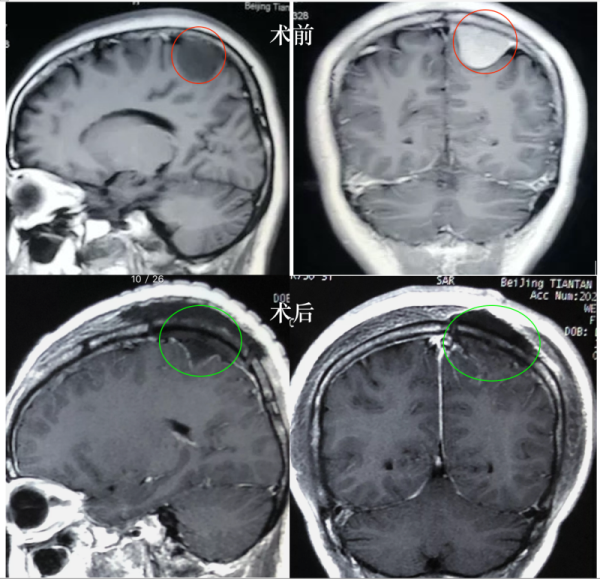

【脑瘤治疗案例汇总】INC曾接诊的这四个真实的疑难脑瘤手术案例或许正能解答大家的这些疑问。就这些案例患者而言,术前教授都曾给到他们明确的可以...

大脑镰旁脑膜瘤 是指位于大脑纵裂并与大脑镰相连的一类临床上常见的 脑膜瘤 ,常突入一侧大脑半球内,有时可向双侧发展。其中大多数是良性的,恶性...

从MRI和CT影像上来看,肿瘤的控制成功,没有肿瘤残余,也并无手术并发症的产生。建议2-3年再次复查MRI。这是INC国际神经外科顾问团的德国Helmut Bertalanf...